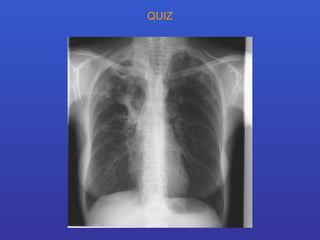

QUIZ